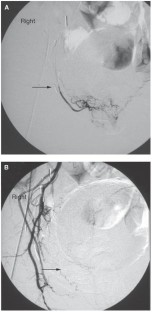

Prostatic hematuria can be a challenging clinical problem. In this Review we discuss the spectrum of methods for diagnosing prostatic hematuria and the pharmacologic and minimally invasive therapies currently available to treat primary disease and refractory cases. Before making a diagnosis and starting therapy, however, other, nonprostatic sources of hematuria must be ruled out. As part of diagnosis all patients should undergo a formal cystoscopy. Therapy should include functional and biochemical approaches. Inhibitors of 5-α-reductase have been shown to successfully treat prostatic hematuria when it is caused by benign prostatic hyperplasia. Intravesical instillations, using agents such as alum, silver nitrate and formalin, have been used as second-line therapies, with limited success. A novel, minimally invasive method, termed selective arterial prostatic embolization, offers another option for treating prostatic hematuria. Using interventional radiologic techniques during selective arterial prostatic embolization enables selective catheterization of the prostatic arterial circulation with subsequent embolization. This approach can rapidly stop hematuria. If more-invasive therapy is required, transurethral resection, or vaporization of the prostate and clot evacuation, should be performed before embolization or other surgical interventions.

In patients with refractory hematuria, selective arterial prostatic embolization provides a minimally invasive treatment option

Rastinehad AR et al.: Selective arterial prostatic embolization (SAPE) for refractory hematuria of prostatic origin. Urology, in press